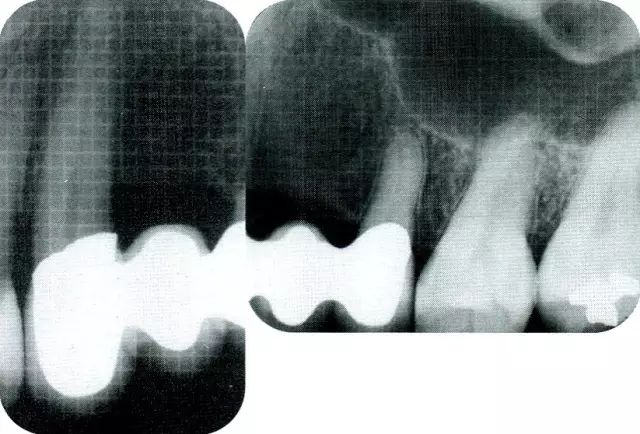

▲圖7-2  術(shù)前x片。確認(rèn)存在垂直性深骨缺損。